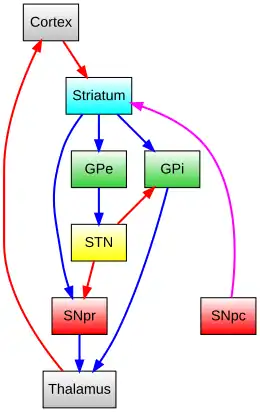

The substantia nigra (SN) is a basal ganglia structure located in the midbrain that plays an important role in reward and movement. Substantia nigra is Latin for "black substance", reflecting the fact that parts of the substantia nigra appear darker than neighboring areas due to high levels of neuromelanin in dopaminergic neurons.[1] Parkinson's disease is characterized by the loss of dopaminergic neurons in the substantia nigra pars compacta.[2]

Although the substantia nigra appears as a continuous band in brain sections, anatomical studies have found that it actually consists of two parts with very different connections and functions: the pars compacta (SNpc) and the pars reticulata (SNpr). The pars compacta serves mainly as a projection to the basal ganglia circuit, supplying the striatum with dopamine. The pars reticulata conveys signals from the basal ganglia to numerous other brain structures.[3]

Afferent connections

The main input to the SNpr derives from the striatum. It comes by two routes, known as the direct and indirect pathways. The direct pathway consists of axons from medium spiny cells in the striatum that project directly to pars reticulata. The indirect pathway consists of three links: a projection from striatal medium spiny cells to the external part of the globus pallidus; a GABAergic projection from the globus pallidus to the subthalamic nucleus, and a glutamatergic projection from the subthalamic nucleus to the pars reticulata.[6][7] Thus, striatal activity via the direct pathway exerts an inhibitory effect on neurons in the (SNpr) but an excitatory effect via the indirect pathway. The direct and indirect pathways originate from different subsets of striatal medium spiny cells: They are tightly intermingled, but express different types of dopamine receptors, as well as showing other neurochemical differences.

Significant projections occur to the thalamus (ventral lateral and ventral anterior nuclei), superior colliculus, and other caudal nuclei from the pars reticulata (the nigrothalamic pathway),[8] which use GABA as their neurotransmitter. In addition, these neurons form up to five collaterals that branch within both the pars compacta and pars reticulata, likely modulating dopaminergic activity in the pars compacta.[9]

The substantia nigra is an important player in brain function, in particular, in eye movement, motor planning, reward-seeking, learning, and addiction. Many of the substantia nigra's effects are mediated through the striatum. The nigral dopaminergic input to the striatum via the nigrostriatal pathway is intimately linked with the striatum's function.[10] The co-dependence between the striatum and substantia nigra can be seen in this way: when the substantia nigra is electrically stimulated, no movement occurs; however, the symptoms of nigral degeneration due to Parkinson's is a poignant example of the substantia nigra's influence on movement. In addition to striatum-mediated functions, the substantia nigra also serves as a major source of GABAergic inhibition to various brain targets.

Pars reticulata

The pars reticulata of the substantia nigra is an important processing center in the basal ganglia. The GABAergic neurons in the pars reticulata convey the final processed signals of the basal ganglia to the thalamus and superior colliculus. In addition, the pars reticulata also inhibits dopaminergic activity in the pars compacta via axon collaterals, although the functional organization of these connections remains unclear.

The GABAergic neurons of the pars reticulata spontaneously fire action potentials. In rats, the frequency of action potentials is roughly 25 Hz.[11] The purpose of these spontaneous action potentials is to inhibit targets of the basal ganglia, and decreases in inhibition are associated with movement.[12] The subthalamic nucleus gives excitatory input that modulates the rate of firing of these spontaneous action potentials. However, lesion of the subthalamic nucleus leads to only a 20% decrease in pars reticulata firing rate, suggesting that the generation of action potentials in the pars reticulata is largely autonomous,[13] as exemplified by the pars reticulata's role in saccadic eye movement. A group of GABAergic neurons from the pars reticulata projects to the superior colliculus, exhibiting a high level of sustained inhibitory activity.[14] Projections from the caudate nucleus to the superior colliculus also modulate saccadic eye movement. Altered patterns of pars reticulata firing such as single-spike or burst firing are found in Parkinson's disease[15] and epilepsy.[16]

Pars compacta

The most prominent function of the pars compacta is motor control,[17] though the substantia nigra's role in motor control is indirect; electrical stimulation of the substantia nigra does not result in movement, due to mediation of the striatum in the nigral influence of movement. The pars compacta sends excitatory input to the striatum via D1 pathway that excites and activates the striatum, resulting in the release of GABA onto the globus pallidus to inhibit its inhibitory effects on the thalamic nucleus. This causes the thalamocortical pathways to become excited and transmits motor neuron signals to the cerebral cortex to allow the initiation of movement, which is absent in Parkinson's disease. However, lack of pars compacta neurons has a large influence on movement, as evidenced by the symptoms of Parkinson's. The motor role of the pars compacta may involve fine motor control, as has been confirmed in animal models with lesions in that region.[18]